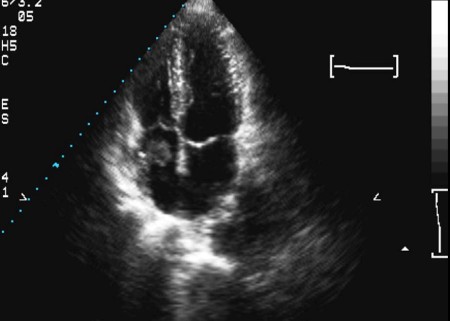

There may be no differences in symptoms and signs. [Figure caption and citation for the preceding image starts]: Two-dimensional echocardiogram of a right atrial thrombus (note: not attached to septum)From the collection of Dr Syed Wamique Yusuf, Department of Cardiology, University of Texas MD Anderson Cancer Center; used with permission [Citation ends].

Echocardiogram or MRI/CT scan will reveal the thrombus. Echocardiogram will also identify the catheter that is commonly associated with the formation of the thrombus. Rarely a transvenous biopsy may be indicated.